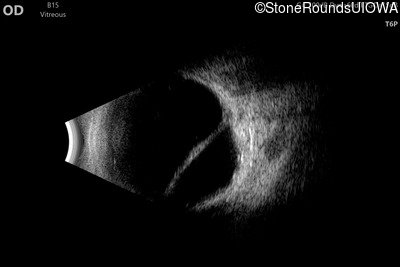

B-Scan Ultrasonography - Right - 20/600

Exemplar